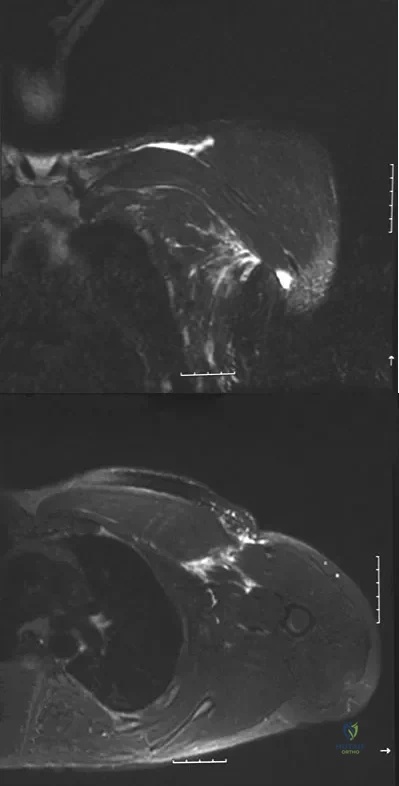

Figures 49a and 49b show MRI scans of the shoulder. What is the most likely diagnosis?

Explanation